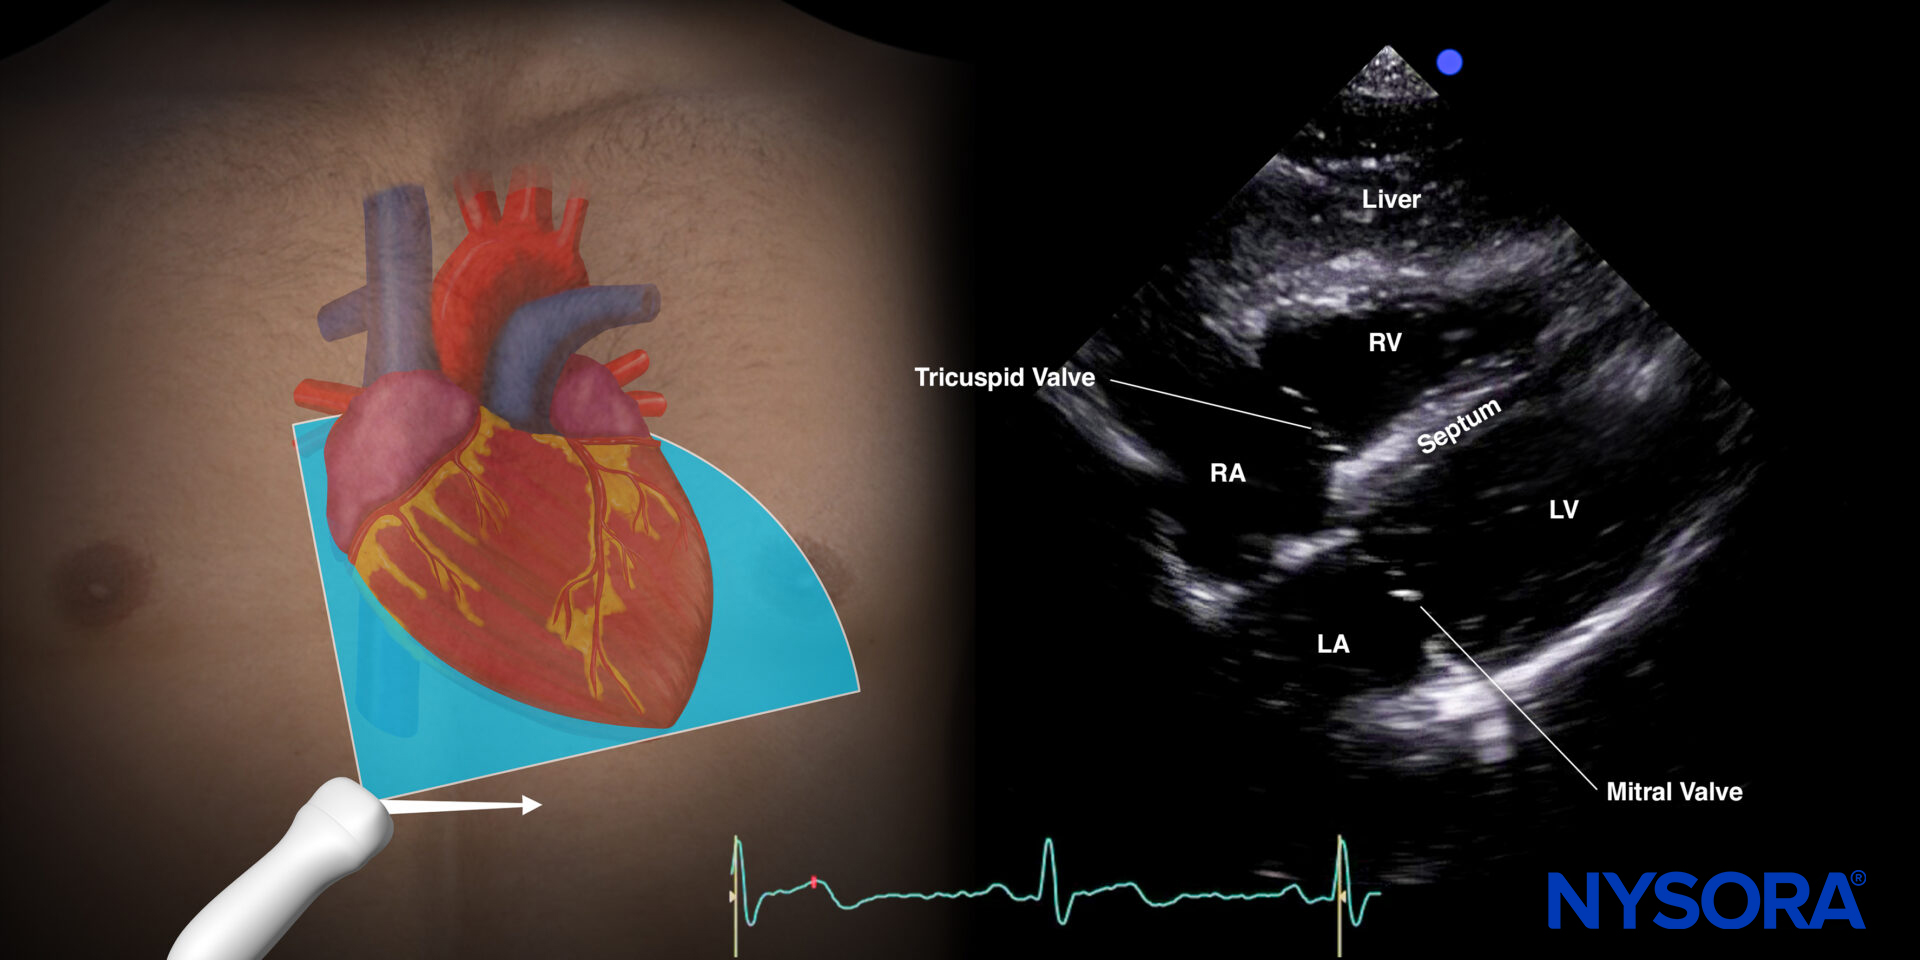

Subcostal four-chamber view (S4C)

Transducer position and sonoanatomy of the subcostal four-chamber view.